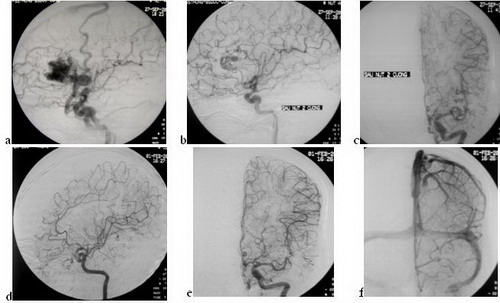

Trường hợp 4: tổn thương còn sau nút nhưng khỏi hoàn toàn sau 6 tháng

Hình 4: Bệnh nhân nam, 42 tuổi, co giật đi khám và chụp CLVT phát hiện DDĐTMN; chụp mạch (21.09.06): ổ dị dạng vùng trán trước trái, kích thước 2.7 x 3,2 cm, tĩnh mạch dẫn lưu nông (Spetzler-Martin II), gồm 2 cuống nuôi từ ĐM não trước (a); nút mạch (27.09.06): cuống 1 bơm 1.2ml với tỷ lệ Histoacryl/Lipiodol: 0.5ml/2.0ml, cuống 2 bơm 1.1ml với tỷ lệ Histoacryl/Lipiodol: 0.5ml/1.5ml; chụp kiểm tra sau nút trên tư thế thẳng (b) và nghiêng (c) thấy tắc gần hoàn toàn, chỉ còn nhánh nuôi rất nhỏ. Chụp kiểm tra sau khoảng 6 tháng (01.02.07), tư thế chếch trái (d), thẳng thì động mạch (e) và thì tĩnh mạch (f): tắc hoàn toàn ổ dị dạng, không thấy tĩnh mạch dẫn lưu cả thì động mạch và thì tĩnh mạch. Sau nút và đến nay (sau một năm) không có biểu hiện dấu hiệu thần kinh.

Tiêu chuẩn vàng của can thiệp nội mạch là làm tắc hoàn toàn và vĩnh viễn ổ dị dạng và bảo tồn được các nhánh mạch bình thường . n-BCA là vật liệu gây tắc vĩnh viễn, ngay sau can thiệp chụp kiểm tra có thể thấy ổ dị dạng được tắc hoàn toàn. Chúng tôi có 2 trường hợp có thể tắc gần như hoàn toàn chỉ còn cuống nuôi rất nhỏ lưu lượng thông rất thấp, trong những trường hợp này chụp kiểm tra sau 3- 6 tháng thấy tắc hoàn toàn (H.4); chúng tôi cũng có 3 trường hợp lưu lượng thông tăng lên và cuống nuôi đủ lớn và nút tiếp cũng được gây tắc hoàn toàn.